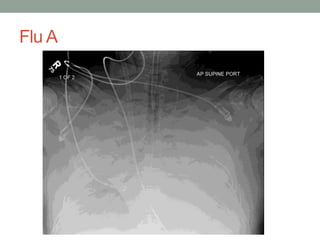

Flu A

ECMO